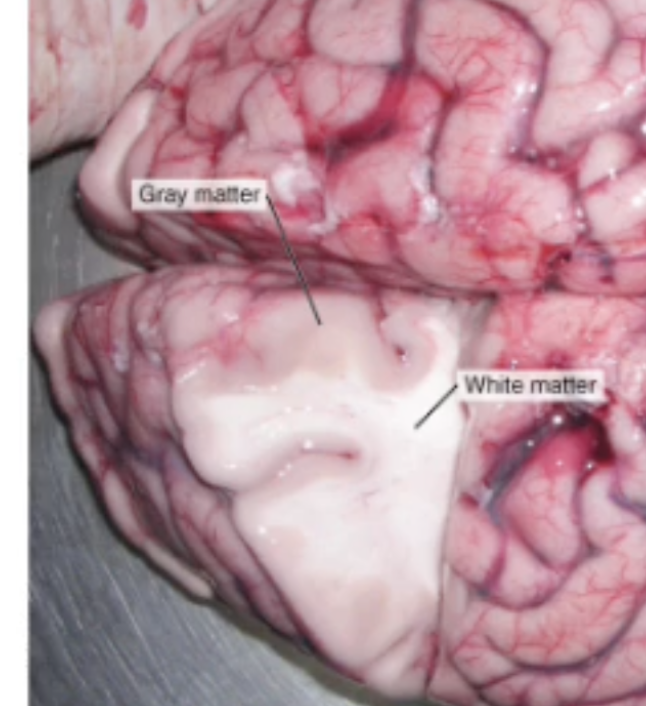

In the Spinal Cord, where is the Grey matter and White matter located

Grey matter is deep (inside), and White matter is superficial

In the CNS, what are groups of neuron cell bodies called? (Grey Matter)

Nuclei

In the CNS, what are bundles of axons called? (White Matter)

Tracts or Fibers